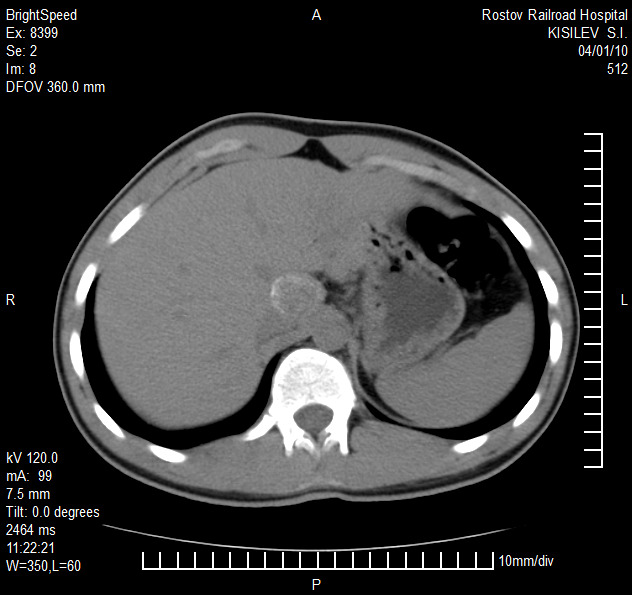

Представлены клинические наблюдения редкого осложнения эхинококкоза печени – прорыва эхинококковой кисты в желчные протоки. Осложнение стало причиной обструкции желчных протоков, механической желтухи и холангита. Освещены этапы диагностики, роль УЗИ в выявлении осложнений эхинококкоза печени, рассмотрены способы минимально инвазивного лечения с применением эндоскопических и чрескожных технологий под контролем лучевых методов.